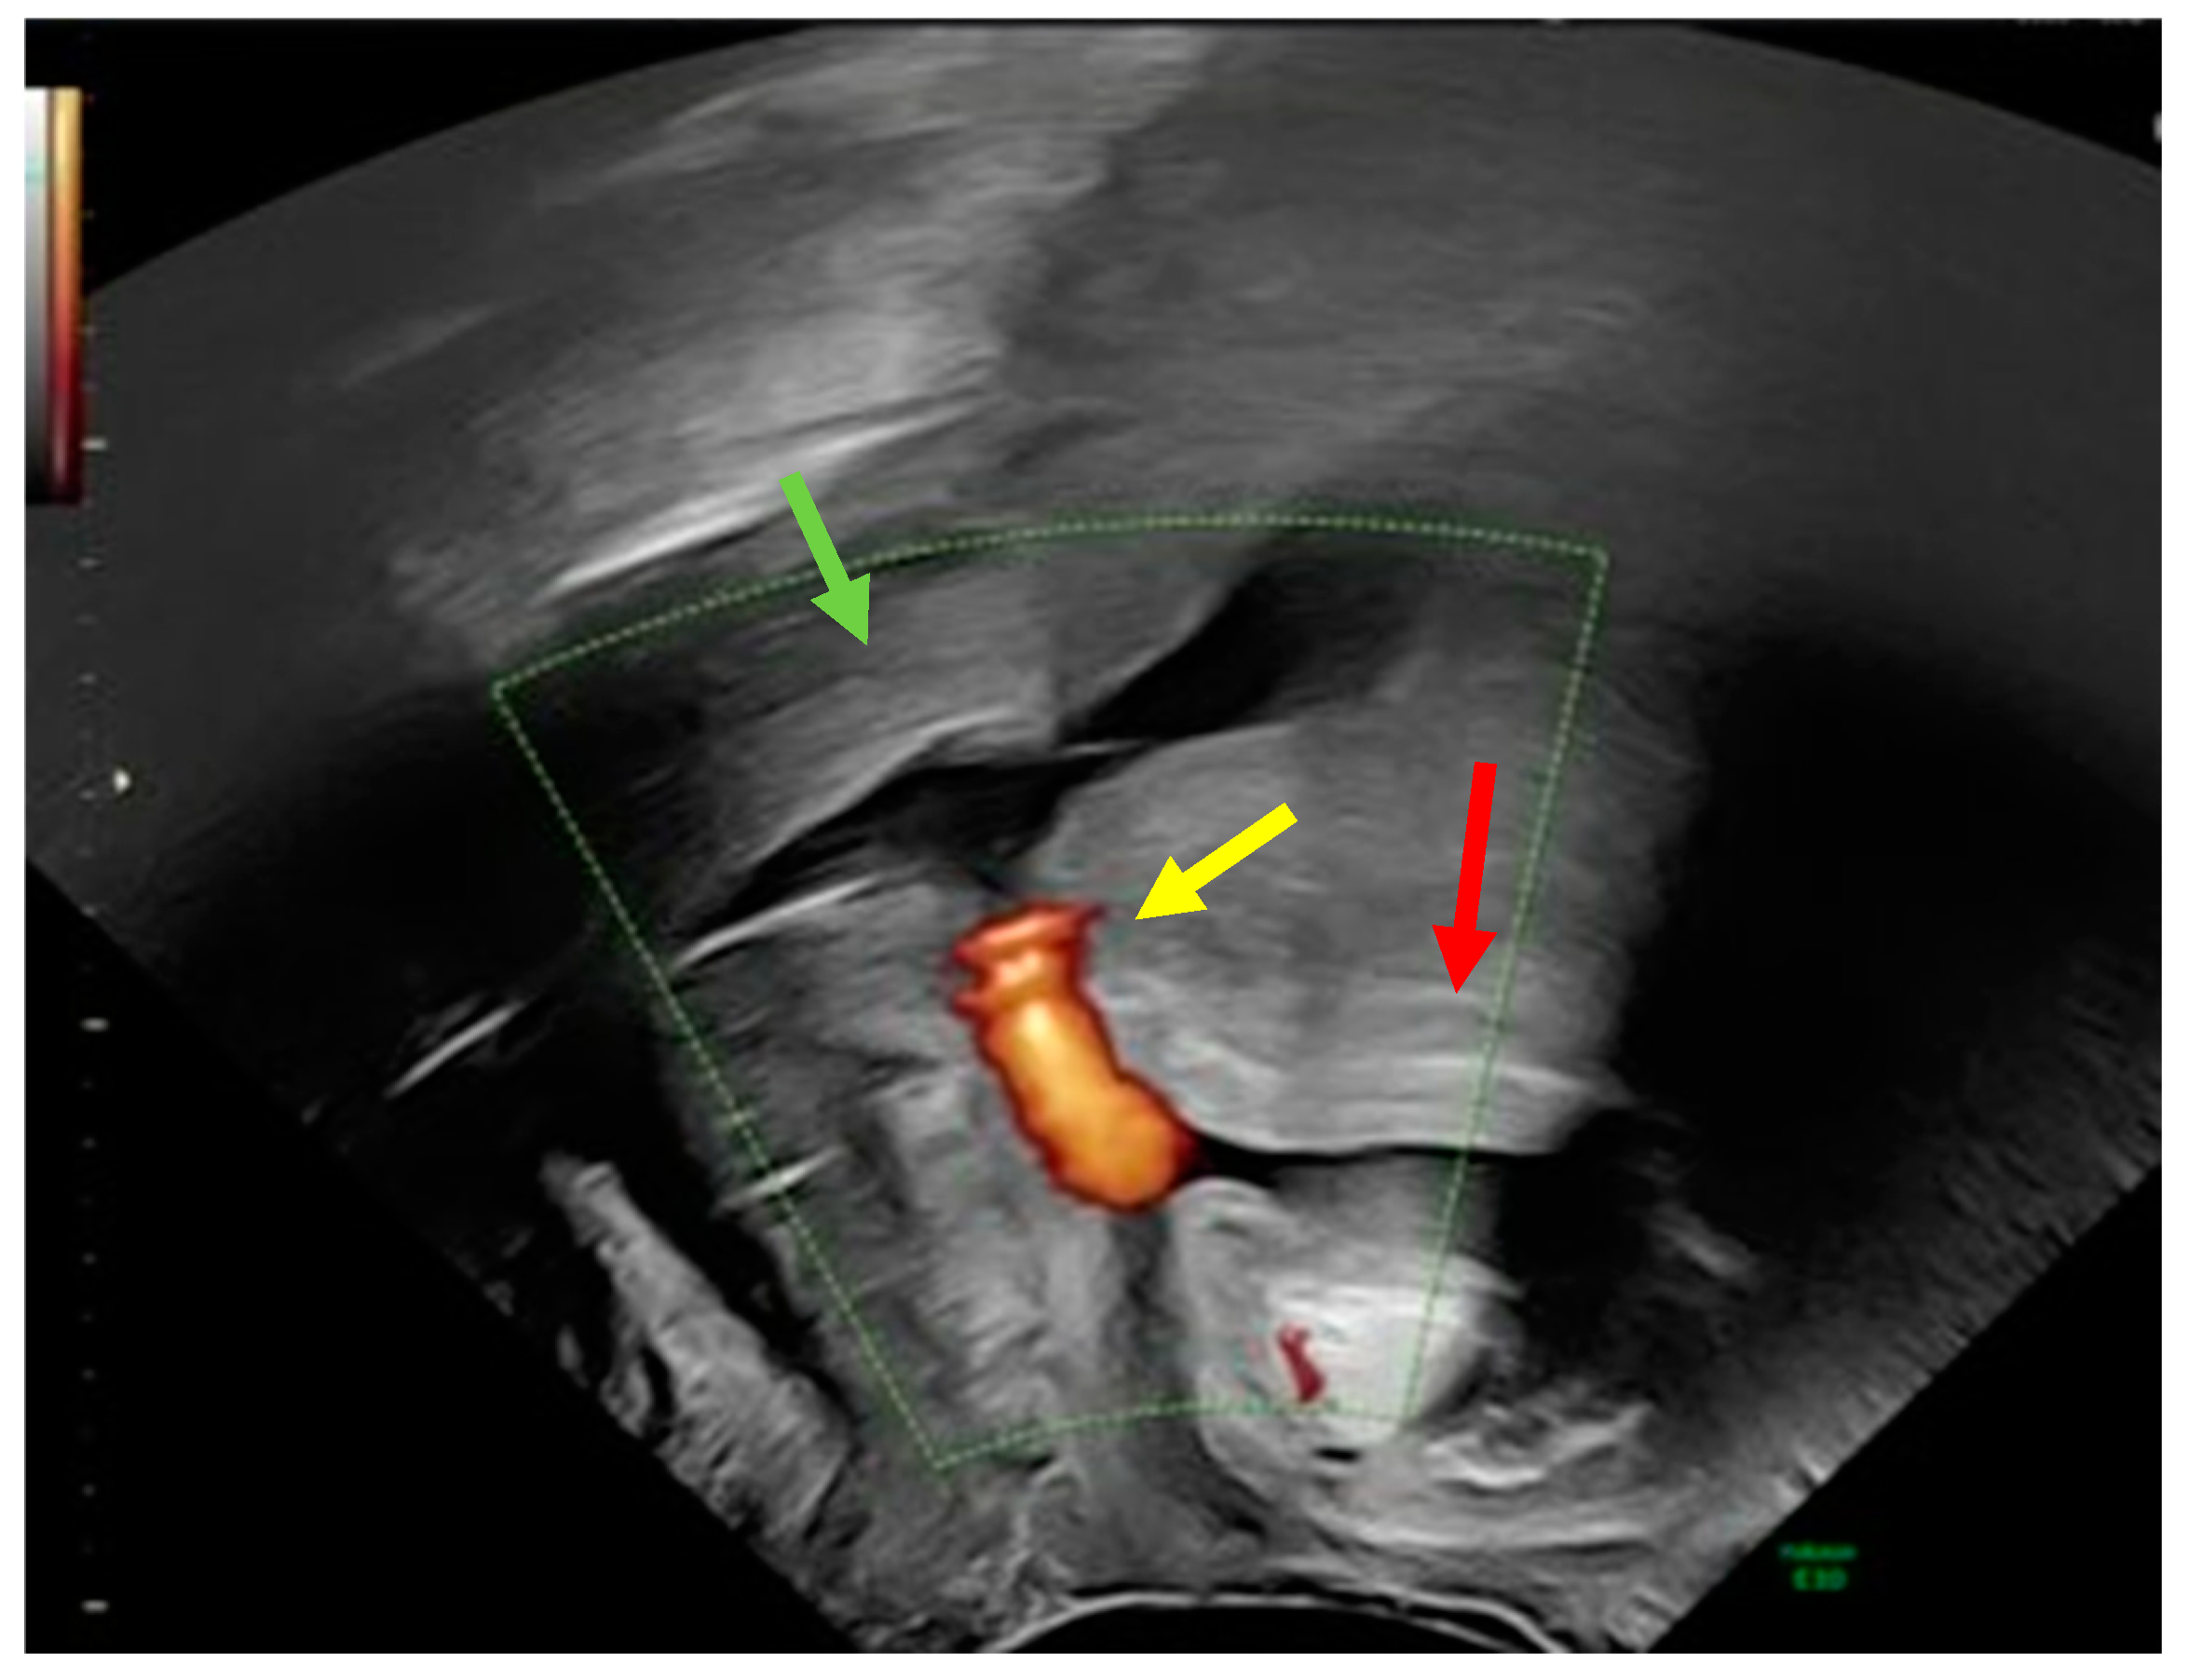

Adhesiolysis revealed a fistula between the urinary bladder and the uterus. The presence of sutures from a previous caesarean section most likely caused this abnormal communication. The abnormal tract between the two organs was removed using partial cystectomy, cystography, and partial myomectomy. Reconstruction was performed using a multilayer technique (Figure 3).

Figure 3.

Multiple layers of sutures of the vesico urinary (black arrow) and uterus (yellow arrow).